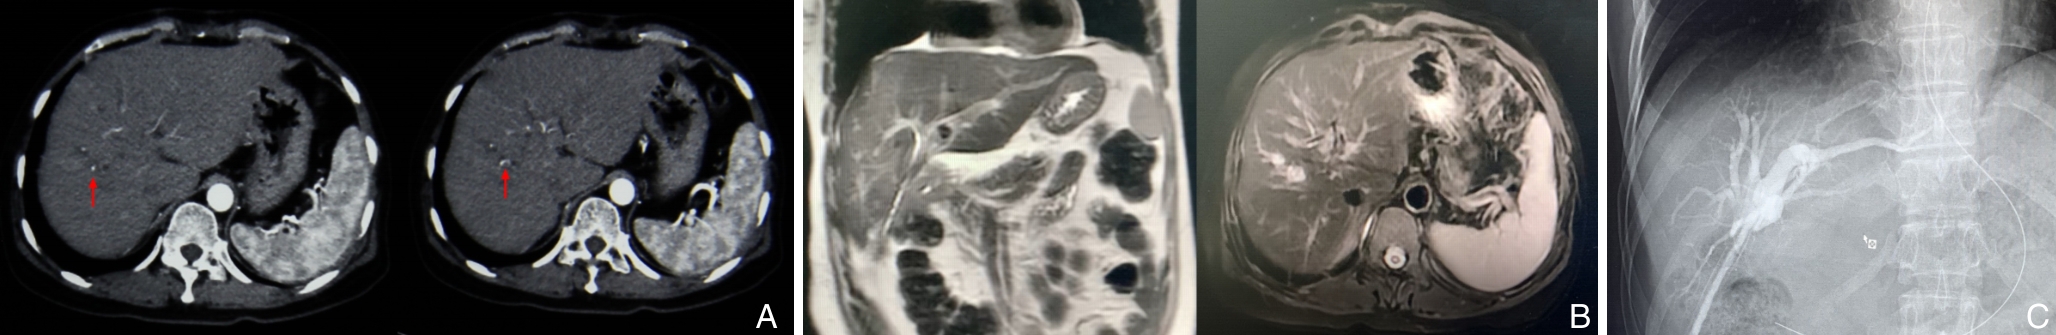

摘要:医源性胆管损伤(IBDI)是常见的胆管损伤类型,多发生于胆囊切除术。随着腹腔镜胆囊切除术的普及,其发生率明显高于开腹手术,且合并血管损伤(VI)的复杂病例逐渐增多,增加了诊治难度,严重时可导致肝缺血及萎缩。肝管空肠吻合术是胆管损伤后常用的重建方式,若合并VI,则可能需行肝切除。本文报告笔者收治的1例53岁女性患者,因胆囊切除术后出现胆汁漏入院。经2次多学科团队(MDT)讨论,术前评估显示肝右动脉及门静脉分支损伤并伴右前叶萎缩。根据术中所见,最终实施右半肝切除联合左肝管空肠Roux-en-Y吻合术。患者术后恢复顺利,随访6个月无明显不适。通过对该病例的诊治过程及文献的回顾与分析,本文总结了复杂IBDI的临床特点、诊治策略及MDT模式的价值,以期为临床实践提供借鉴。